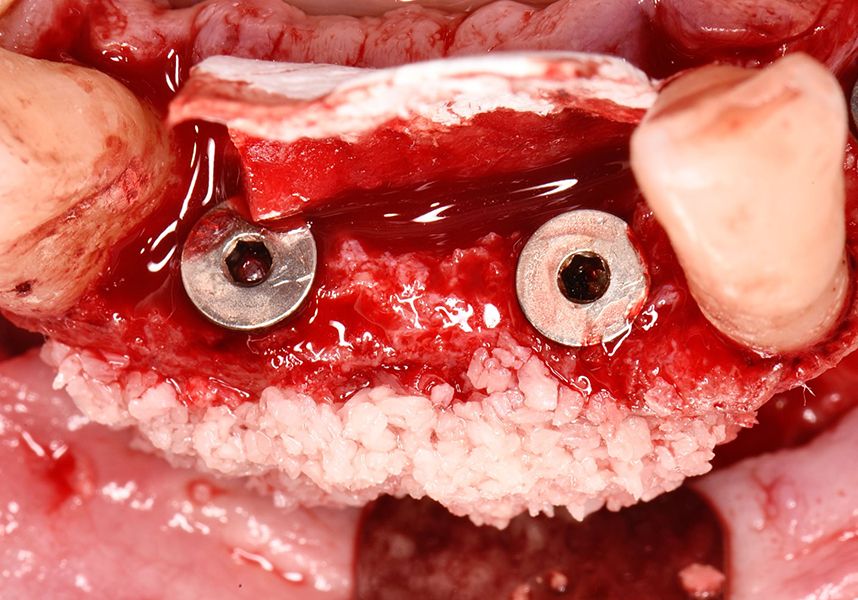

The patient was anesthetized and a flap was made from the distal area of tooth 43 up to 36. Then two Avinent Biomimetic Ocean IC implants of 3.5x10 were inserted in positions 32 and 42.

Respecting the three-dimensionally correct position of the implant led to bone fenestration, leaving the apical part of the apex of the implant exposed almost to the mid-point of its length at 42 and a third in 32.

To treat the defect, bone regeneration was carried out simultaneous to the surgical process, with an autologous bone graft from the patient. In the internal part of the graft we used autologous cortical bone obtained by scraping (Safescraper) and from the biological drilling, at low revolutions and without irrigation, from the other implant beds. In the external layer of the regeneration we used a xenograft (Genoss, Osteogenos) and this was covered with a reabsorbable collagen barrier membrane (Evolution STD, Osteogenos).

The membrane was sutured with PGA reabsorbable suture to the periosteum to secure it, thus avoiding subsequent reentry to remove fixings such as tacks.